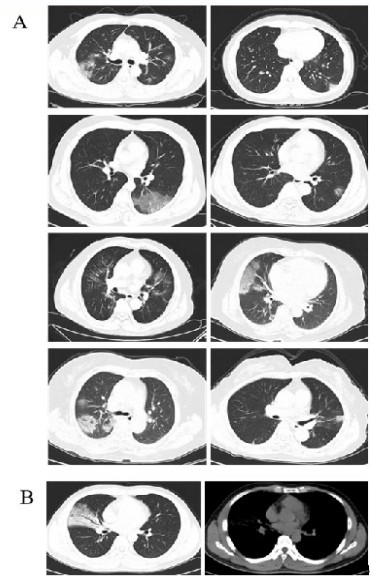

新型冠状病毒感染组患者胸部CT均有肺炎表现,其中8例为磨玻璃影,1例为实变影,见表 3和图 1。非新型冠状病毒感染组中有21例患者胸部CT正常。本研究所筛查的46例患者中,胸部CT正常者的新型冠状病毒核酸检测均阴性。

| A:8例患者在就诊时胸部CT可见磨玻璃影;B:1例患者就诊时胸部CT表现为实变影 图 1 新型冠状病毒感染患者胸部CT表现 Fig 1 The image characteristics of novel coronavirus infection patients |